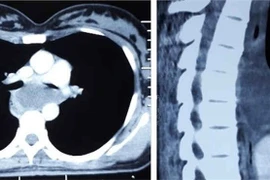

Các bác sỹ khoa Ngoại lồng ngực Bệnh viện K đã tiến hành phẫu thuật thành công, bóc tách khối u kích thước lớn trung thất sau vùng ngực bụng dính vào tĩnh mạch chủ dưới, dính một phần động mạch chủ bụng và phổi phải.

Ung thư vú thường di căn màng phổi, trung thất và hạch vú trong…Tổn thương di căn phổi thường là khối u đặc, dưới 3 cm ở vùng ngoại vi của phổi. Các di căn này thường không có triệu chứng và thường được xác định nhờ chụp Xquang.